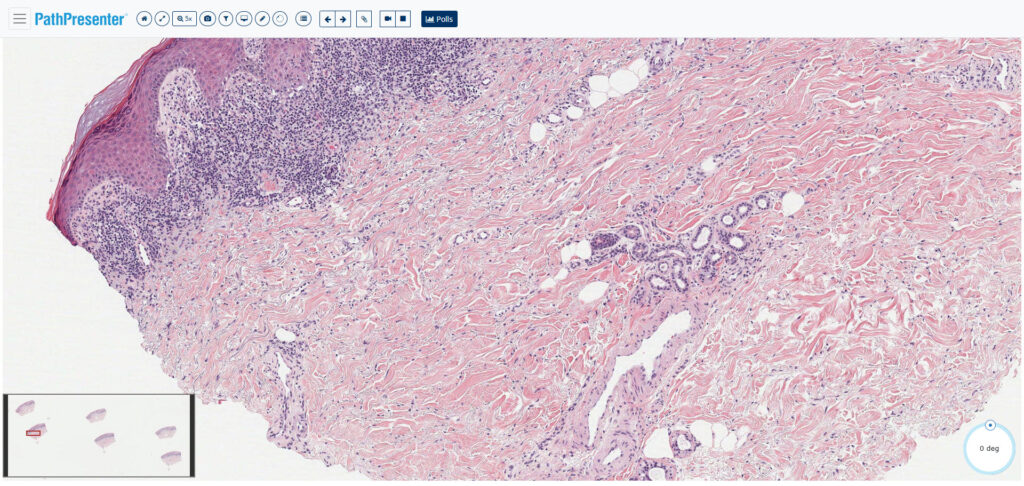

Dermatopathology Review: Case #4

Test yourself with this gold-standard dermatopathology case, curated by leading specialists with decades of experience (including our own Rajendra Singh MD). Check the history, scrutinize the interactive WSI with our viewer, and make your diagnosis. Can you get it? Good luck!